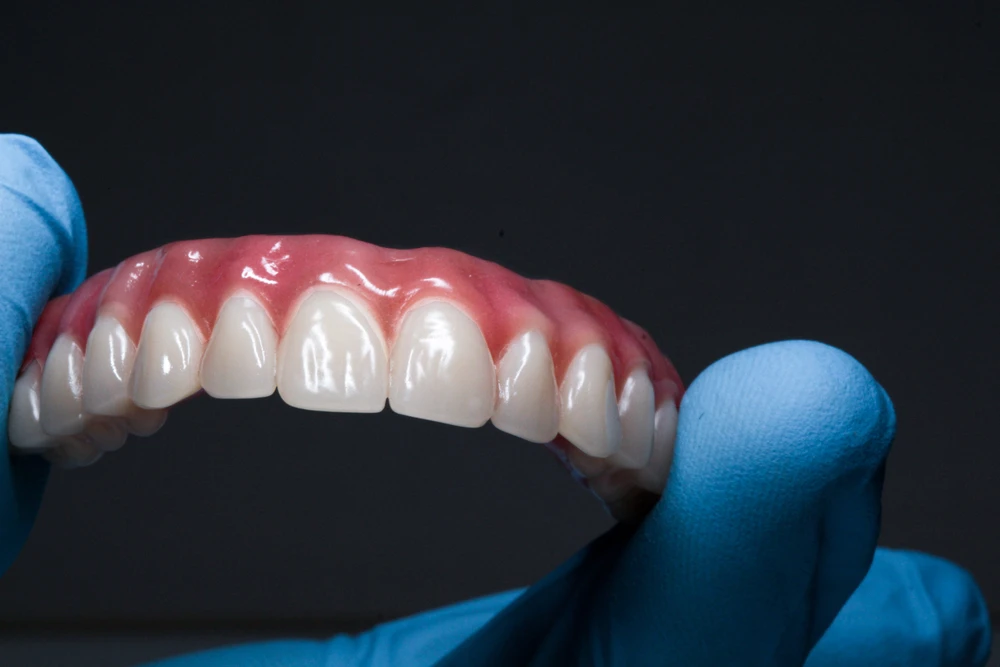

All-on-4 implant tedavisi, tüm dişlerinizi tek seans içerisinde çıkartılıp yerine 4 adet implant üzerine sabitlenen bir köprü ile değiştirmektir. Bu tedavi yöntemi, diş eksiklikleri olan kişilere daha hızlı ve daha kolay bir diş restorasyonu sağlar.

All-on-4 implant tedavisi, uzun vadede en etkili çözümlerden biridir. İmplantlar doğru bakımla ömür boyu kullanılabilir ve kalıcı bir köprü ile birlikte normal dişler gibi kullanılabilir.